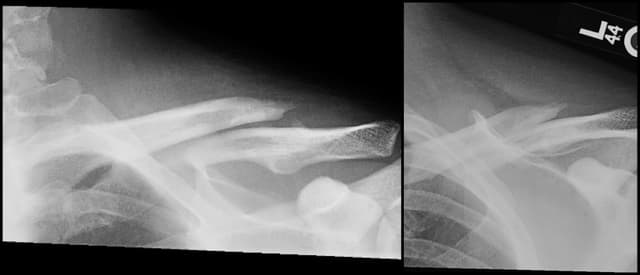

Pre-op

Post-op